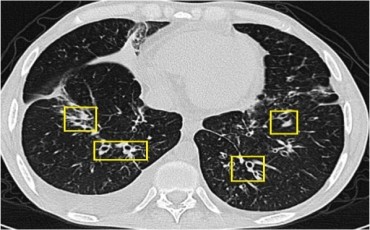

Önce şüphelenmek gerekir. Ardından görüntüleme yapılır. Radyolojik incelemelere Akciğer grafisi ilk basamaktır. Ardından Bilgisayarlı tomografi ve PET/ BT gelir. Burada kitle görüldüğünde bronkokopi ile tanı konulur. Bronkokopi yetmez yada ulaşamazsa dışarıdan iğne ile biyopsi alınır. Buda tanıya katkı sağlamaz ise Cerrahi olarak biyopsi alınır.

Sık öksürük ve bol balgam çıkartma yakınması olan hastayı gören göğüs hastalıkları uzmanı bronşektazinin tanısını once muayene sonra radyoloji ile koyabilir. En iyi inceleme bilgisayarlı tomografidir.

Daha az ışın kullanıldığından ve tüm hastanelerde olduğundan bu gün dünyada düz akciğer filmi taramada kullanılmaktadır. Ancak bu filmler

bilgisayarlı tomografiler kadar detaylı sonuç vermezler. Çok düşük ışınla bilgisayarlı tomografi çeken cihazlar yaygınlaşmaktadır. Bu olanak varsa

3 boyutlu görüntüde verebildiğinden Bilgisayarlı düşük ışınlı tomografiler daha hassas görüntü verir.

Akciğer kanseri şüphesi varsa kesin tanı için biyopsi yapılmalıdır. Bu kitlenin yeri ve tipine göre yapılır. Kitle akciğerin merkezinde ise bronkoskopi,

dışına doğru ise dışarıdan iğne ile biyopsi yapılır. Bazı hastada ikisi birden gerekebilir.